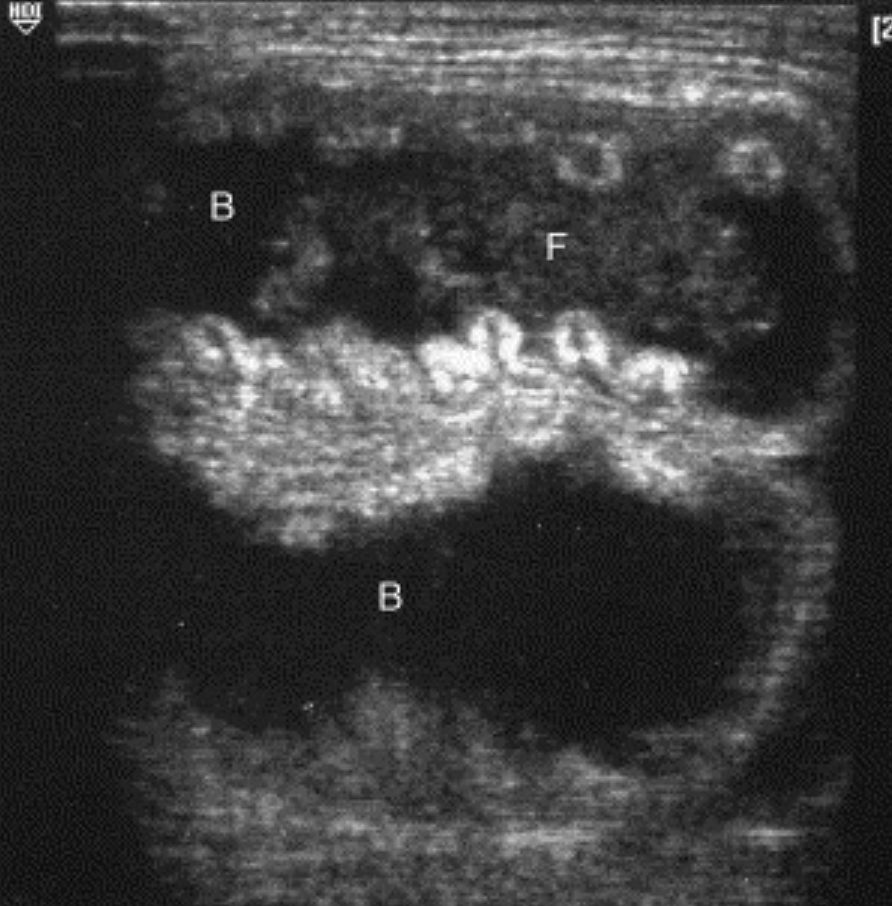

Two loops of bowel (B) with fecal matter (F) in the scrotum. Source: Blaivas & Brannam, 2004.

- Findings: Scrotal hernia appears as bowel or omentum within the scrotum. Peristalsis and flow suggest viability, while dilated, akinetic bowel indicates possible strangulation.